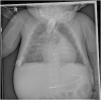

Recibió tratamiento con prostaglandinas hasta los 5 meses de vida, cuando recibió un trasplante cardiaco. Seis meses después del mismo, persistía la hiperostosis en los controles radiológicos (fig. 3).

Radiografías después del trasplante y del fin de tratamiento con prostaglandinas. A) A los 3 meses, B) a los 4 meses, C) a los 6 meses. En ellas se sigue observando hiperostosis y ensanchamiento de los huesos, sin mejoría ni resolución tras el cese de las prostaglandinas. Las vértebras y pelvis no parecen estar afectadas. Tampoco se observa afectación mandibular.